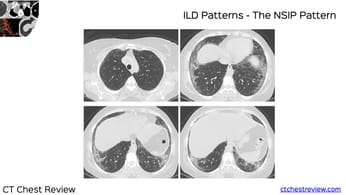

Interstitial Lung Disease